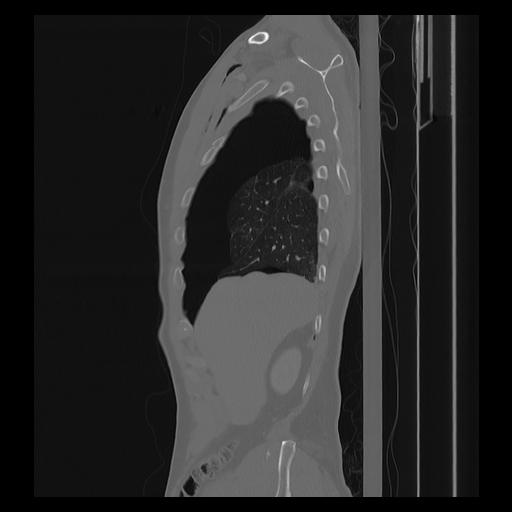

33 PULMON,CE,Sagittal,3.000,PULMON,Sagittal,